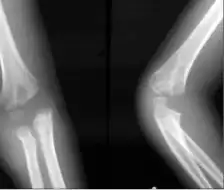

Refracture image shows a lateral condyle fracture with cubitus varus.

Cubitus varus is a varus deformity in which the extended forearm is deviated towards midline of the body.

Cubitus varus is often referred to as "Gunstock deformity", due to the crooked nature of the healing.[1][2]

Cubitus varus is not able to be diagnosed until after healing of the prior fracture, as the arm must be in full extension, not flexion, for the deformity to be noticed.